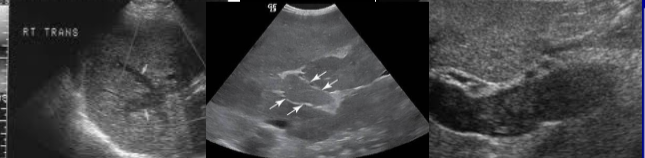

echinococcal cyst (squiggle lines is the water lily sign)